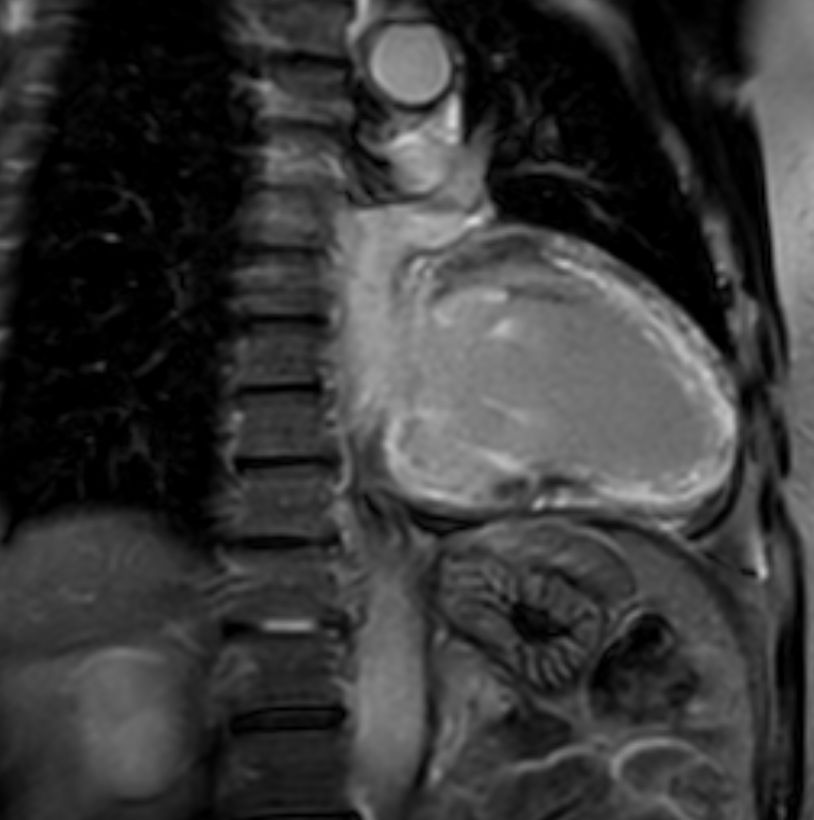

2 chamber view 3D PSIR

2 chamber view cine

2 chamber view T2w Black Blood